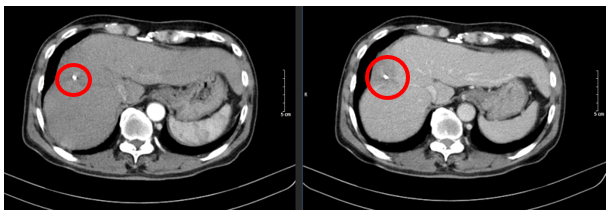

Ngày 27/02/2024: (sau 3 chu kì)

Hình 3: Hình ảnh chụp cắt lớp vi tính ổ bụng: U gan hạ phân thùy VIII (vòng tròn đỏ) kích thước 50x77mm, ngấm thuốc không đều, có thải thuốc sau tiêm sau điều trị, còn tăng sinh mạch, không có huyết khối

Ngày 19/06/2024: (sau 7 chu kì)

Hình 4: Hình ảnh chụp cắt lớp vi tính ổ bụng: Nhu mô vùng ngoại vi sát bao gan hạ phân thùy VII - VIII có đám (vòng tròn đỏ) giảm tỉ trọng kích thước ~ 28x36mm, trong có lắng đọng vật liệu nút mạch, không có huyết khối